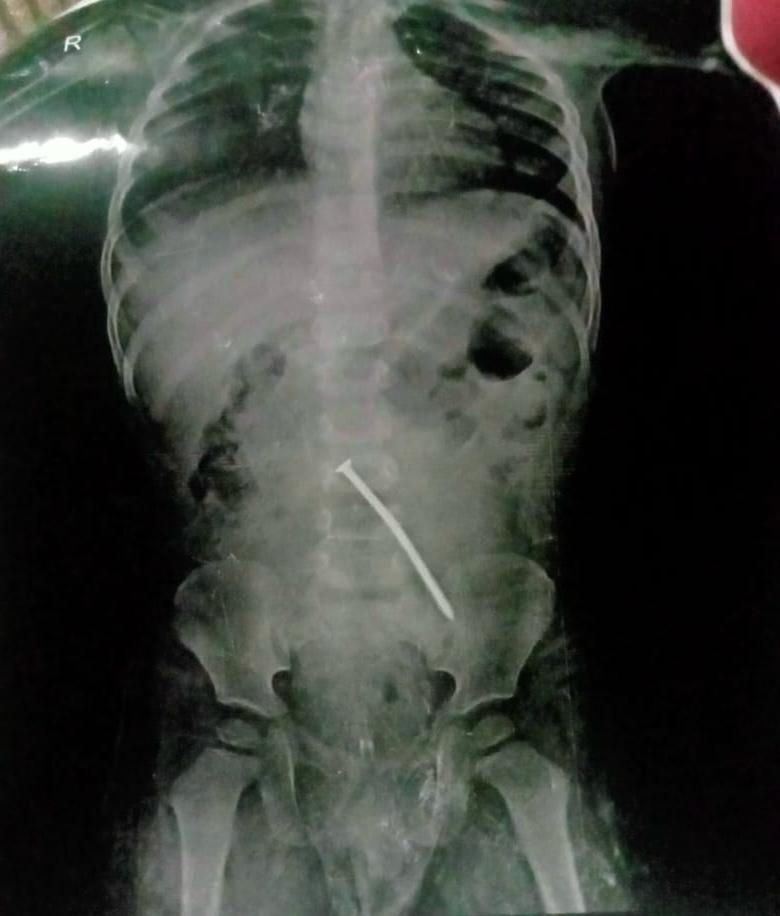

وحدة المناظير بمستشفى الوراق نجحت إزالة مسمار 7 سم من الأمعاء

تمكنت وحدة المناظير بمستشفي الوراق المركزي من إنقاذ حياة طفل ، حيث نجحت الدكتورة إيمان عامر عفيفي استشاري مناظير الجهاز الهضمي ورئيس وحدة المناظير بالمستشفي من إزالة مسمار 7سم من الأمعاء الدقيقه بمنظار المعدة لطفل عمره سنتين بعد ابتلاعه دون ملاحظة الوالدين .